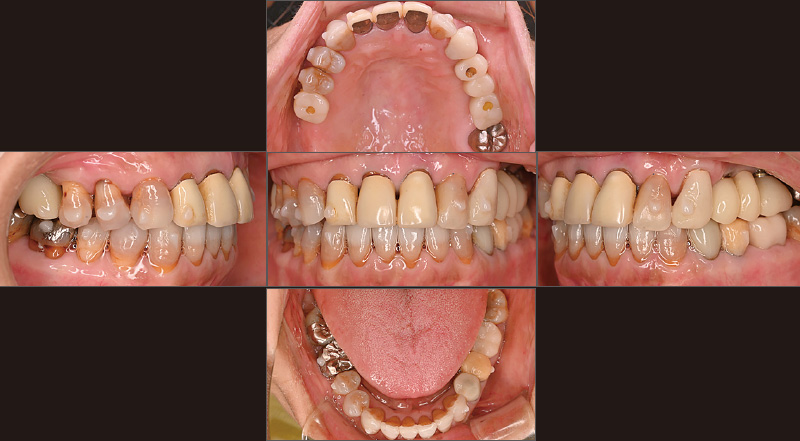

症例の患者さんは「奥歯でものが噛めない」という主訴で初めて来院されました(図1)。義歯治療を行い、いったんは噛めるようになりましたが、噛める位置だけで噛み続けていたためか、徐々に義歯が不安定になり、5年後に再び来院されました(図2, 3)。そこで、義歯を撤去し、インプラント治療に加えて、第一大臼歯まで矯正可能な「iGo Plus」による矯正治療を提案しました。最初に「iGo Plus」のクリンチェック治療計画を行い、矯正治療後の位置を考慮し、インプラント治療の埋入計画を立て、双方の診断画像を照らし合わせ、最終的なインプラント埋入位置を決定しました。計画した位置にインプラントを埋入し(図4)、プロビジョナルを装着しました。その後「iGo Plus」によるクリンチェック治療計画を再度行った後(図5, 6)矯正治療を開始し(図7)、当初の計画通りに矯正治療を完了しました(図8)。ここまでしておけば、噛めなくなる事態は回避できるでしょう。私たちの役目は、咬合状態を回復し、噛める状況まで持っていくことです。その後、審美性を求めて治療を続けていくかは患者さんの判断に委ねます。症例の患者さんの場合は、これから前歯の審美治療を行う方向で相談中です。

図8 2025年5月、歯列が整い、噛める状態になったことで、当院が考えるシンプルな治療は終了。図6と比較し、当初の計画通りに治療が進んだことがわかる。